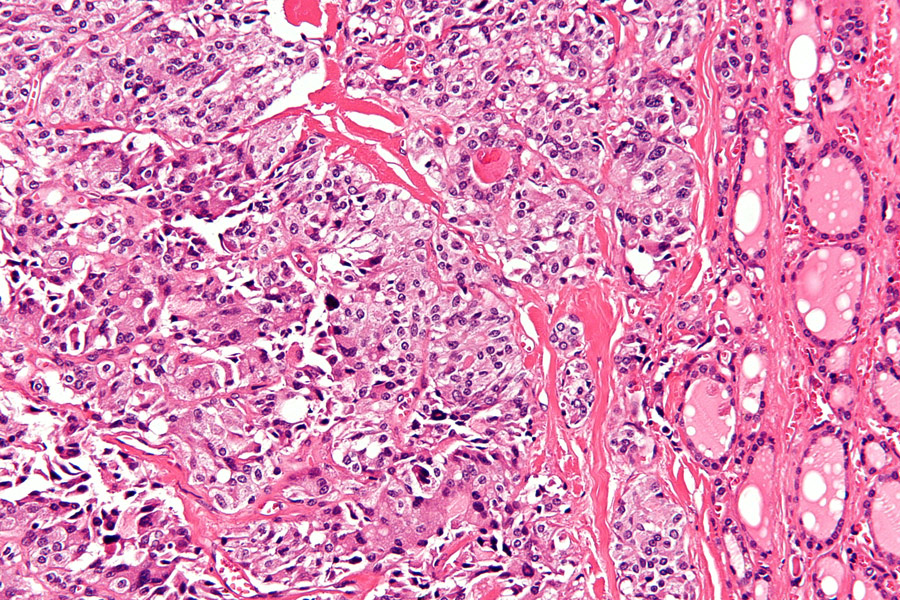

在许多类型癌症中都可以看到这种异常活性RET蛋白,其中包括神经甲状腺癌(MTC)、毛状甲状腺癌(PTC)和非小细胞肺癌(NSCLC)等实验实验证实转基因变异技术基因是这些癌症的原因,并需要异常变频活动使肿瘤细胞保活这使RET成为癌症处理的良好目标

通常情况下,RET激活受规范,但遗传变化可能发生,导致蛋白质持续活化RET可因基因聚合或点变异而变换,其中一些在多内分泌2-影响内分泌Glands这两种变化都会导致不受控RET激活,转而意味着信号路径上的进一步响应也将开机下游效果是细胞增加扩散和生存,引起肿瘤形成